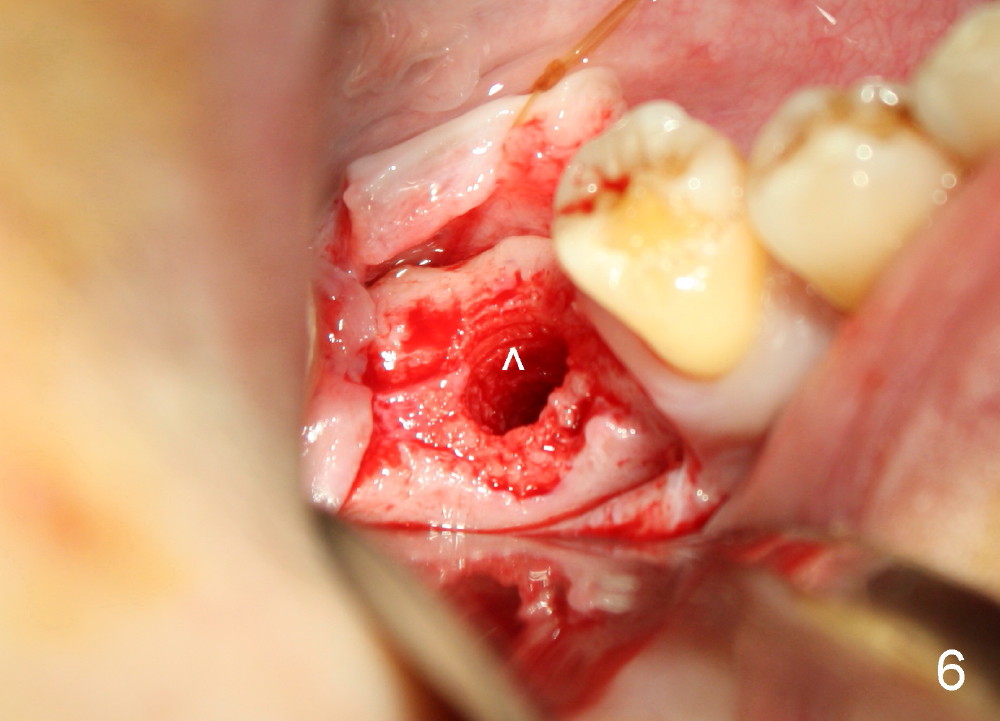

An incision is made instead of flapless, the socket is found to be filled with regenerated bone (Fig.3). After using 2 mm pilot drill, a paralleling pin is inserted to confirm trajectory and distance from the inferior alveolar nerve (Fig.4). Osteotomy is enlarged by Bicon reamers; threads are formed by insertion of Tatum 5x14 mm tap at the depth of 11 mm (Fig.5). The threads are visible when the tap is removed (Fig.6 ^). The advantage of using tap(s) is to test binding to the bone. If the tap is loose, the next sized tap should be used before placing a proper sized implant. This step is particularly critical when placing a large immediate implant or when the socket is immature.